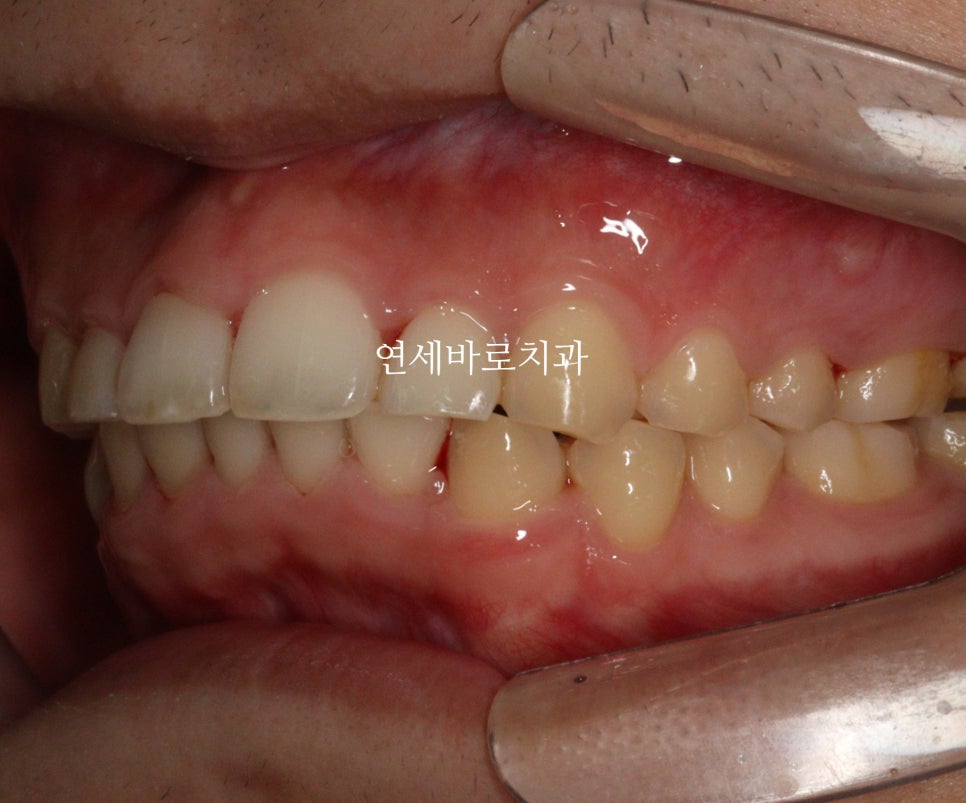

어금니 관계를 보면 1:1 로 만나던 치아가 사이사이 지그재그 들어가는 것이 보이죠?

약 5mm정도 후방이동 된 것으로 보입니다.

워낙 짧은 치관 길이와 골격형태가 교정치료를 하기 어려운 상황이긴 했지만,

환자분이 내원간격도 잘 지켜주시고, 오랜기간 변함없이 잘 참아주셔서 좋은 결과를 얻을 수 있었던 것으로 생각합니다.